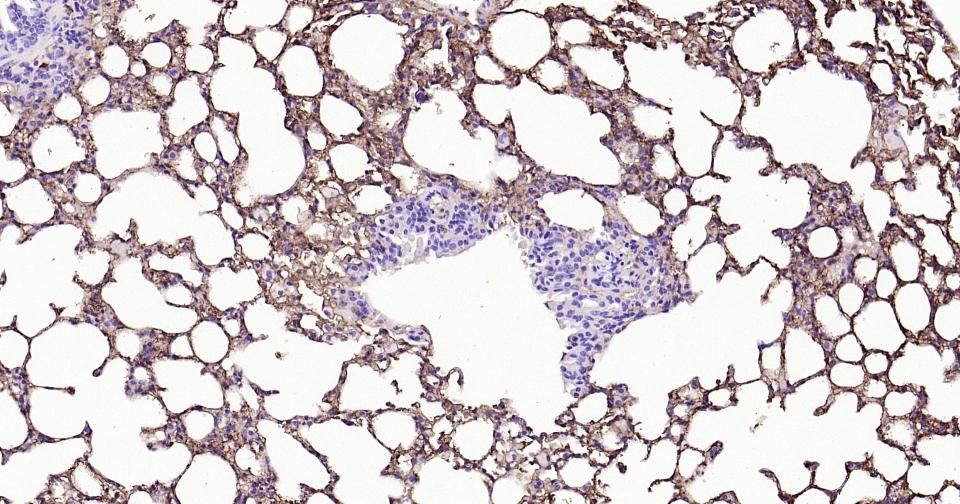

Paraformaldehyde-fixed, paraffin embedded Mouse Lung; Antigen retrieval by boiling in sodium citrate buffer (pH6.0) for 15 min; Antibody incubation with Tau-4 Monoclonal Antibody, Unconjugated(bsm-41804M) at 1:800 overnight at 4°C, followed by conjugation to the SP Kit (Mouse, sp-0024) and DAB (C-0010) staining.